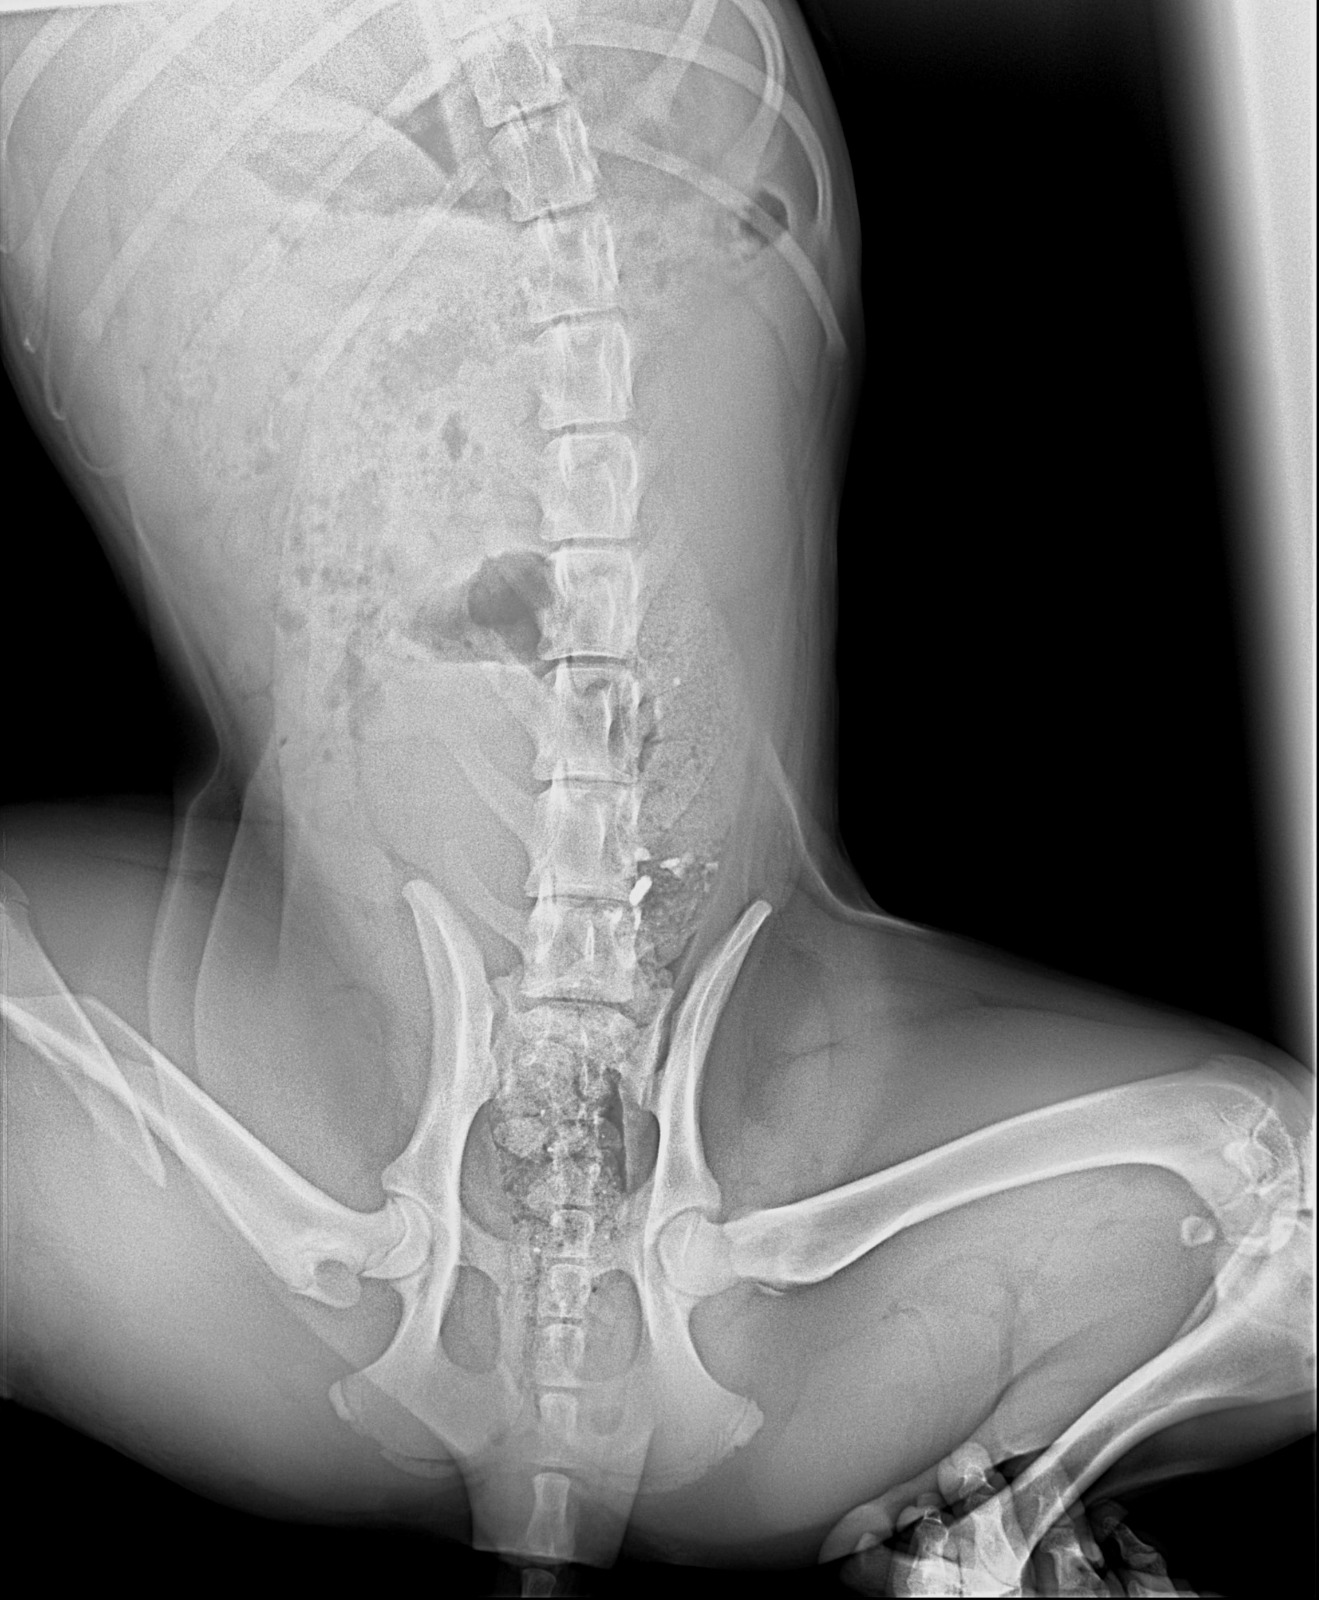

These dogs are in south lebanon rescued from war zone after being left behind. The one to the left was hit by a car and have a broken hip as shows frkm x rays and needs an urgent operation. It costs 650 usd as per the screenshot of chat with the vet. Please your help us needed. We can not afford as we are not working currently.